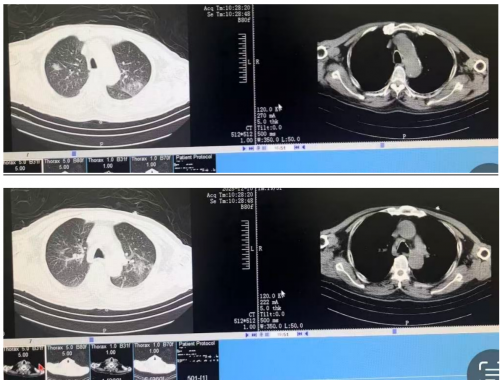

12月07日:

晨测动脉血气(FiO250%):PH7.487,PO2 125mmHg,PCO236.3mmHg,HB 98g/L,K 3.4mmol/1, Ca2+ 1.13mmol/L, Na+ 146mmol/L, Glu 4.6mol/L, Lac 1.3mmol/L, HCO3- 27.5mmol/L,BE 4.0mmol/L。

白细胞 6.82×10^9/L,红细胞3.12↓x10^12/L,血红蛋白96↓g/L,血小板 211×10^9/L,中性粒细胞计数 4.52×10^9/L,淋巴细胞计数 1.30×10^9/L,C反应蛋白 73.23 mg/L。

肺泡灌洗液细菌培养提示假白喉棒杆菌,给予加用“莫西沙星注射液 0.4g qd”抗感染治疗。

12月08日 改鼻导管吸氧3L/min